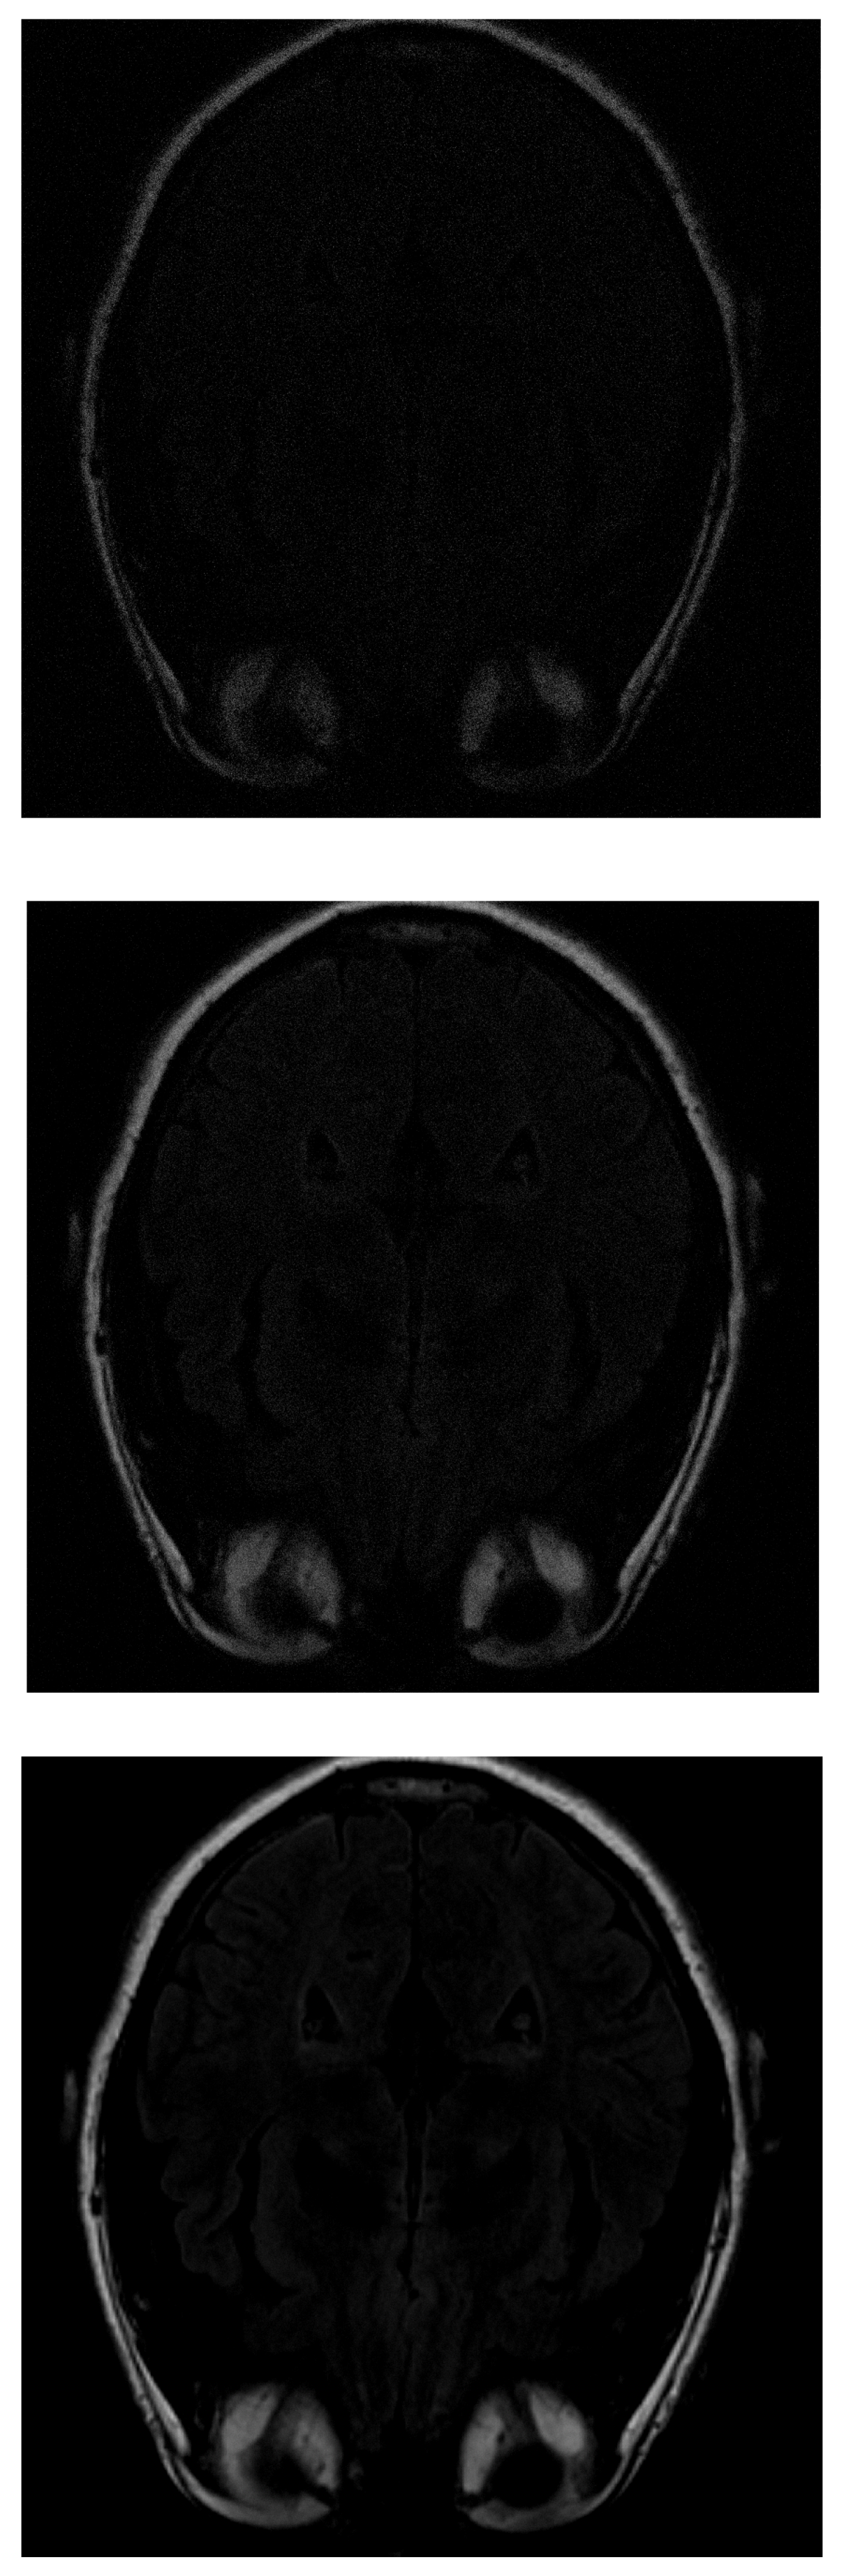

Medical imaging acquisition is greatly enhanced by the use of compressed detection techniques since, as discussed above, it is possible to reconstruct a given signal (image) using only a few random measurements. This can substantially increase the speed and accuracy of the acquisition process and lead to better image qualities for certain medical devices, such as those using MRI, which often take a long time to take. This was verified in this section, which presents results after applying the CS algorithms in medical images obtained with magnetic resonance. Several images of the head of the human body obtained from the database of the University of South Carolina [15] were analyzed. Two images commonly used to assess for medical problems were taken: an axial slice of the brain and an axial section of the face and neck region, both at 2048 × 2048 resolutions. The first image is challenging because the brain area does not have much resolution, and it is difficult to distinguish particular features. The second image shows more contrast between different tissue types and is easier to assess.

One of the images used in the simulations is shown in Figure 3. The image corresponds to an axial section of the brain in the plane marked by the blue lines in Figure 4. In it, the orbit of the eyes can be distinguished in the lower part. Fat appears with a very strong signal, while water and cerebrospinal fluid have a very low intensity.

Figure 4. Images of sagittal, coronal and 3D slices of the brain. The blue line shows the plane corresponding to the image in Figure 3.